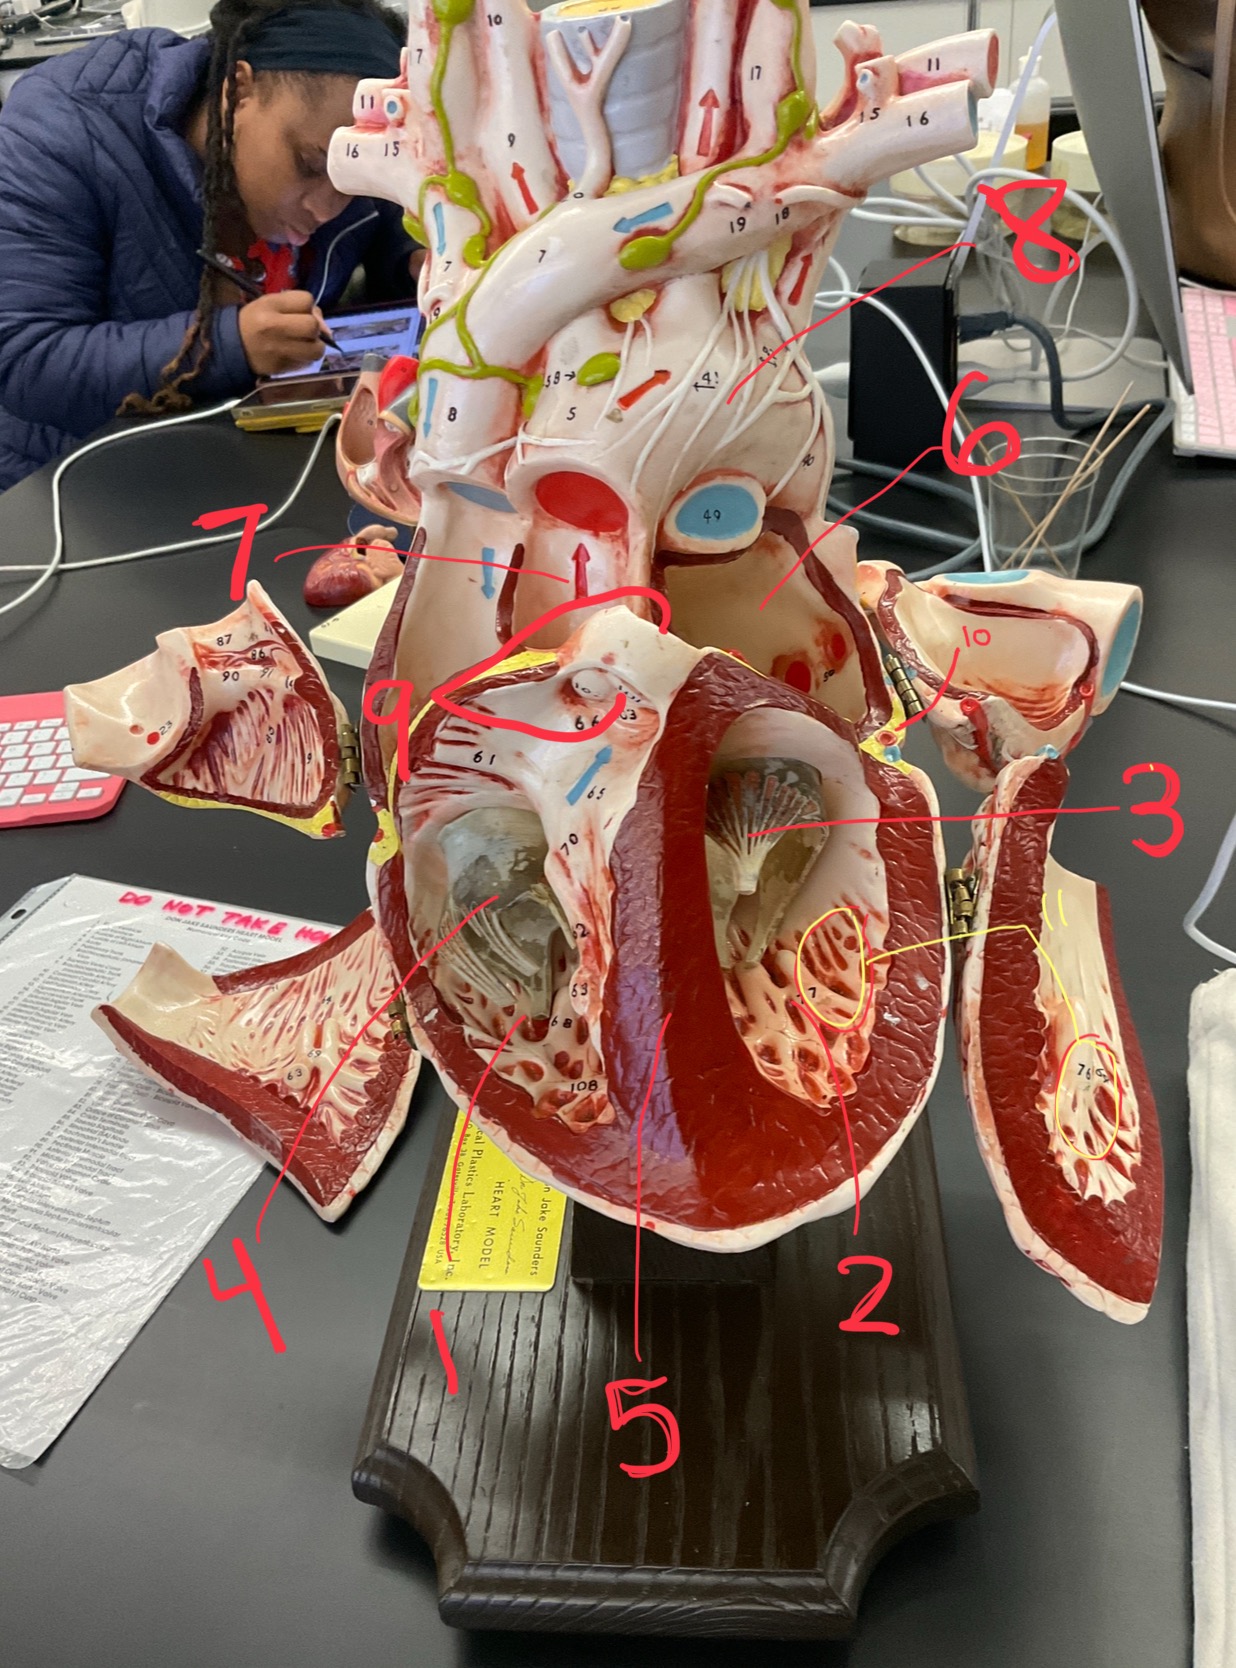

1

epicardium

2

3

endocardium

3

2

myocardium

4

1

coronary sinus

5

2

inferior vena cava

6

3

superior vena cava

7

1

right ventricle

8

2

left ventricle

9

3

bicuspid

10

4

tricuspid

11

5

interventricullar septum

12

6

left atrium

13

7

aorta

14

8

aortic trunk

15

9

pulmonary semi-lunar valve

16

10

atrevoventricullar sulus

17

11 (not smooth part)

trubeculae carneae

18

1

papillary muscle

19

2

chordae tendineae

20

4

pulmonary trunk

21

6

aortic trunk